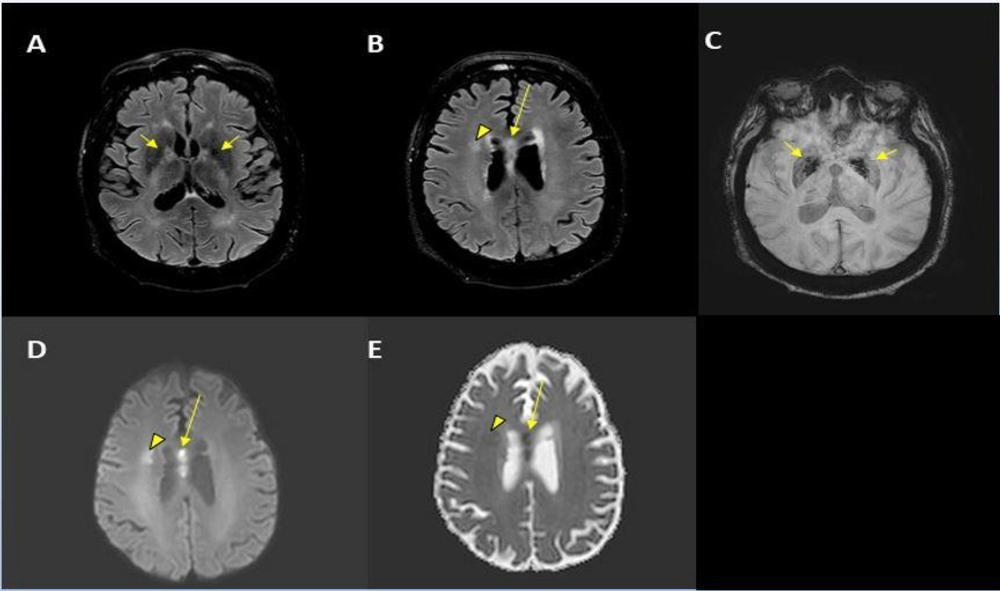

Figure 1. Stroke seen in a 41-year-old male patient with COVID-19 infection.

Figure 2. Acute anterior cerebral artery/middle cerebral artery watershed infarction seen in a 47-year-old male patient who presented with COVID-19 pneumonia. Watershed infarctions occur at the border between cerebral vascular territories where the tissue is furthest from arterial supply and thus most vulnerable to reductions in perfusion, or passage of fluid.